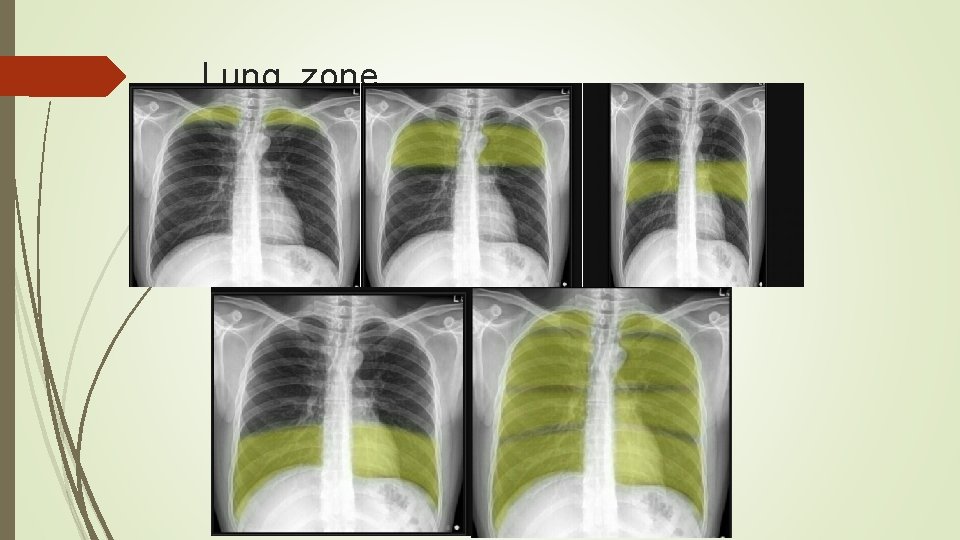

Pediatric imaging Learning objectives 1 Systemic approach interpretation